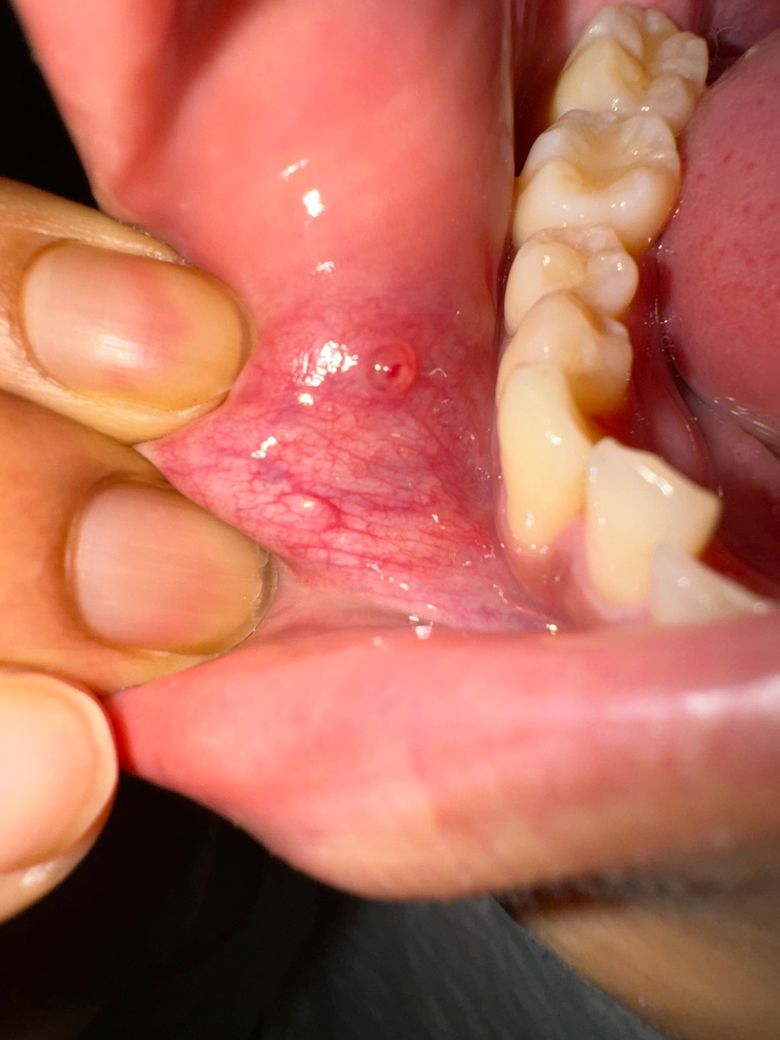

8월 말에 입 안에 첫번째 사진처럼 물집같은게 잡혀서 입안이 불편했습니다. 아프진 않았구요.

그렇게 방치하니 위 사진(생긴지 일주일) 되고 저 위에 알보칠을 바르니 하얗게 일어나면서 (아프지않았습니다) 피같은게 찼습니다. 김치찜같은 자극적인 걸 먹어서 좀 더 커졌나싶기도합니다.

• 1번 째 사진